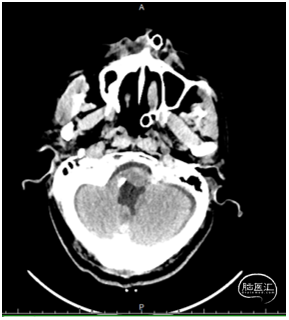

头颅CT:

提示四脑室至枕骨大孔区2.9*2.3cm肿物,内见多发钙化,延髓、四脑室受压